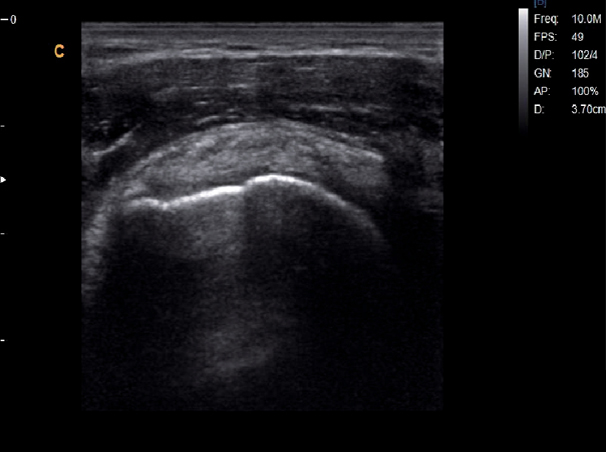

Musculoskeletal,B Mode

Subscapularis Tendon, B Mode